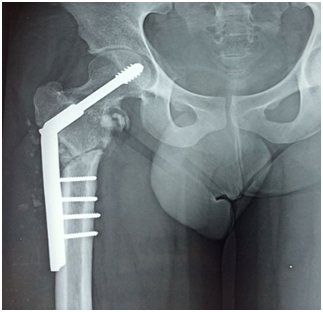

A radiograph of the pelvis revealed a primary non union fracture neck of femur (Figure 1). On MRI, it was found that the femoral head was viable (Figure 2).

Figure 1 Plain radiograph showing non union fracture neck of femur Right side.